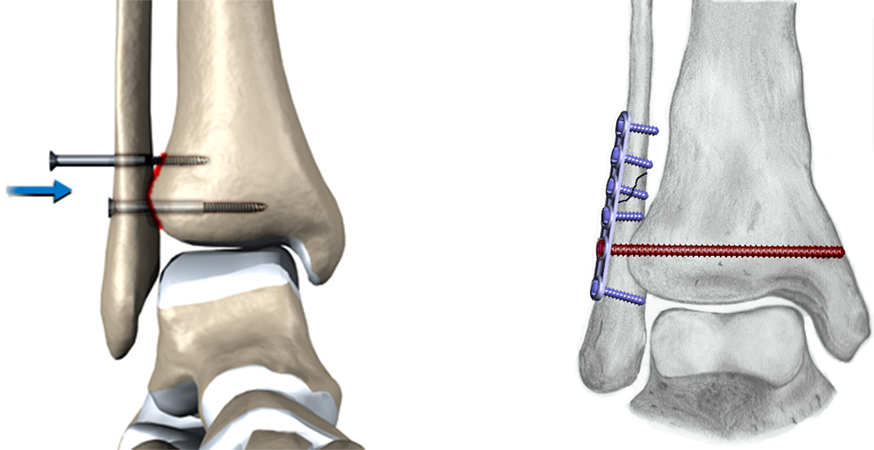

Quando indicado, o tratamento cirúrgico é realizado através da incisão de um ou de ambos os lados do tornozelo, redução dos fragmentos ósseos para a sua posição original e fixação com a utilização de parafusos e placas metálicas.

A lesão ou abertura da articulação tibiofibular (sindesmose) deve ser diagnosticada e tratada cirurgicamente. Neste caso, utiliza-se um longo parafuso ou mecanismo de contenção que mantenha a “pinça” articular fechada e estável até a completa cicatrização ligamentar.